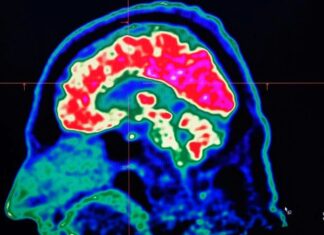

O mundo está ficando mais quente e isso está afetando nossos cérebros